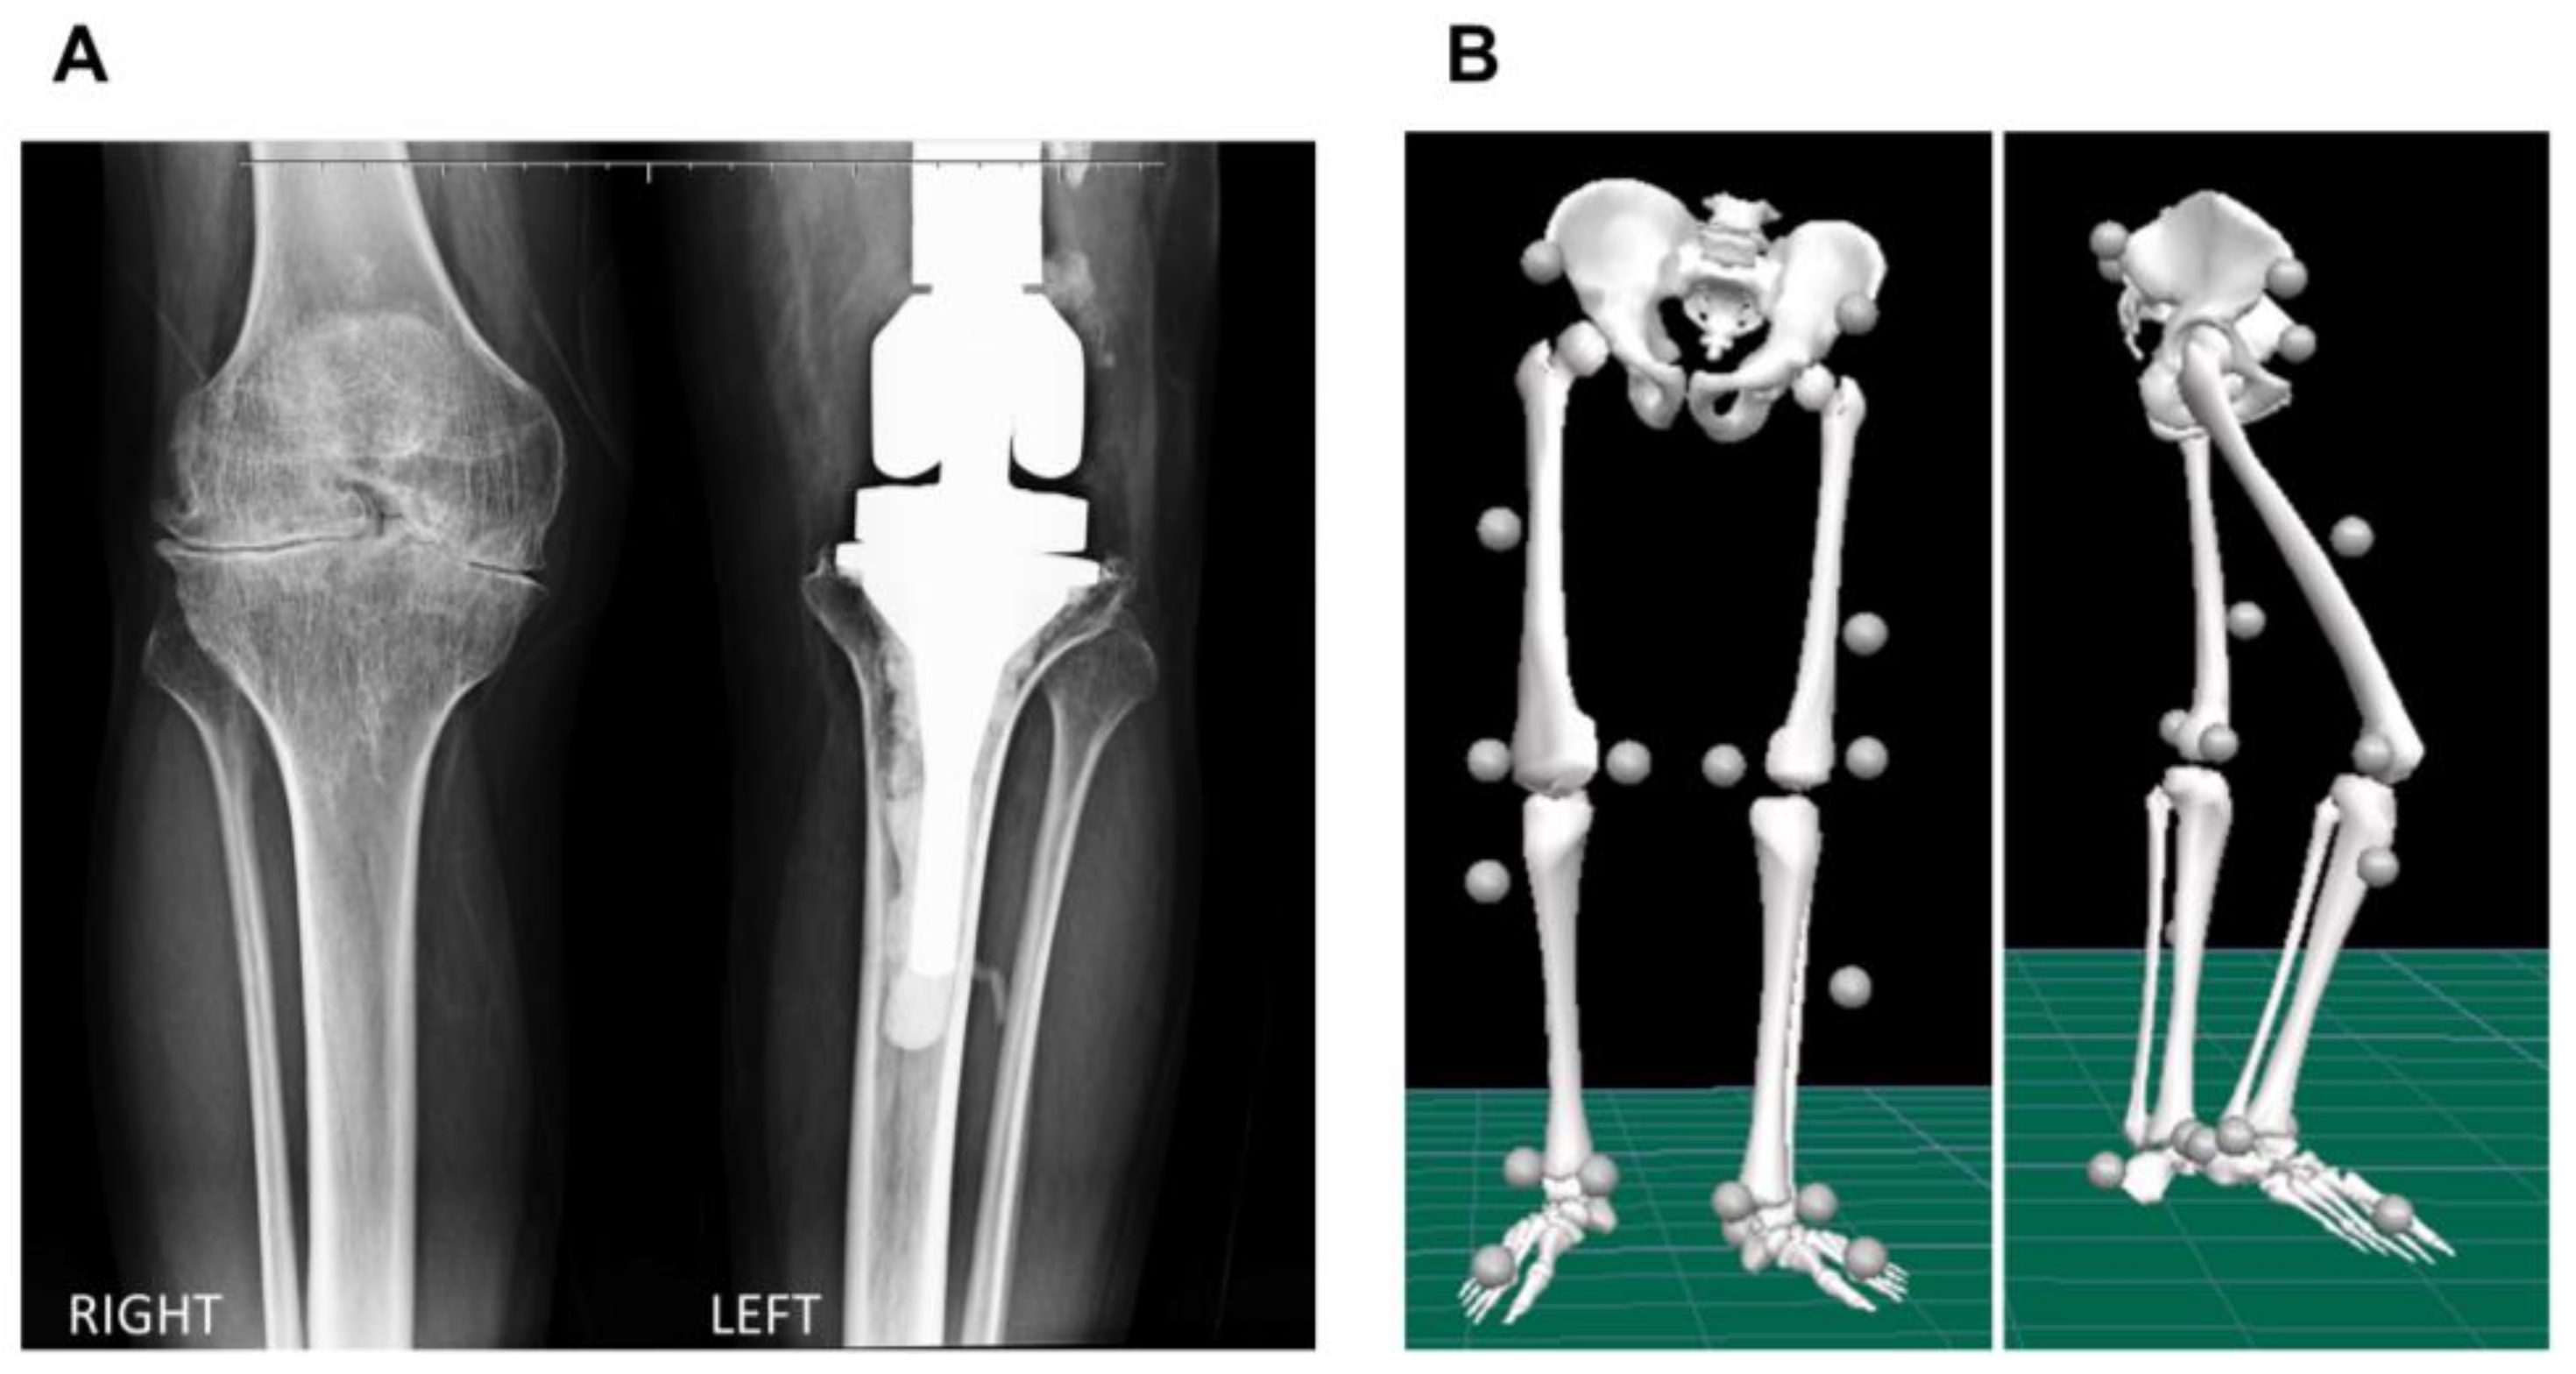

2. Case Report

2.1. Biomechanical Assessment